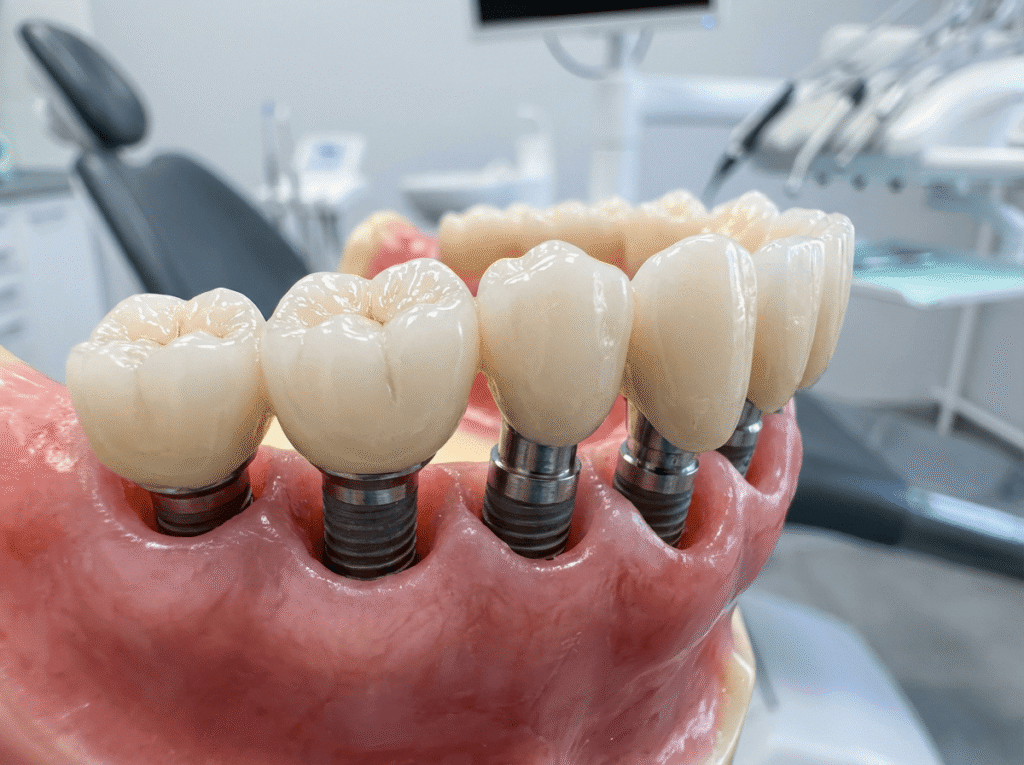

Un sistema implantare completo è composto da tre elementi fondamentali:

- Fixture implantare: la vite in titanio che viene inserita nell’osso e funge da radice artificiale

- Abutment (moncone): il connettore che unisce la fixture alla protesi dentale

- Corona o protesi: la parte visibile che riproduce esteticamente il dente naturale